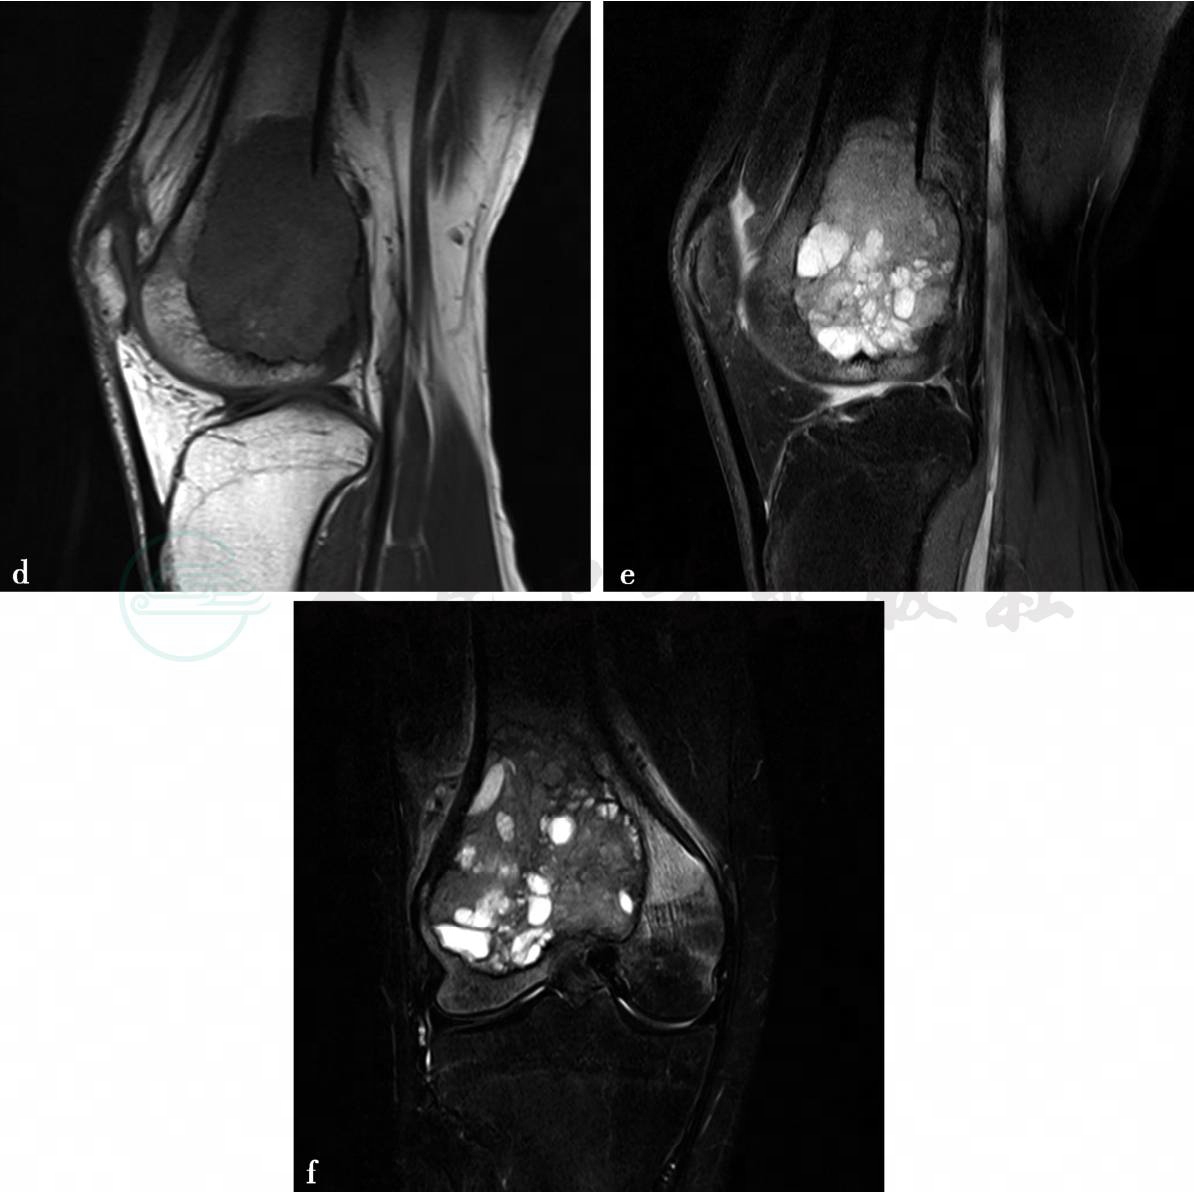

图3 图3d~f,MRI示右股骨远端膨胀性骨质破坏,边界较清楚,病灶组织向后侧略突出皮质外。图3d,病灶内容物在T1WI上呈低信号。图3e、f,在T2WI脂肪抑制像上呈略高信号,在远侧病灶内有多个圆形的更高小囊状信号影,无液-液平面。无明确骨膜反应